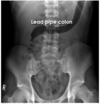

What are the main sites the ulcerative colitis occurs?

What are the pathological features of UC?

What distinguishes UC from Crohn’s Pathologically?